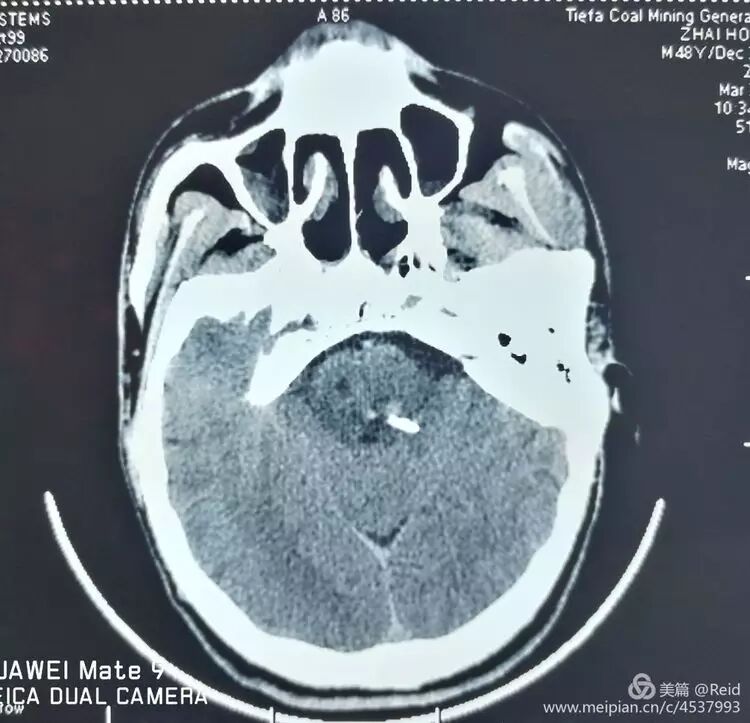

男患,50岁,突发意识障碍2小时入院。既往有高血压病史数年,治疗不规范。入院时病人深昏迷,GCS=1+1+2,双瞳孔2mm,四肢无活动,生命指标正常。入院后家属选择保守治疗。入院24小时后呼吸减慢,<10次/分,浅表,给予呼吸机辅助呼吸。

保守治疗72小时后,病情无明显改善,家属决定尝试外科手术干预,谨慎沟通后,以移动呼吸机辅助下,经CT引导精确定位置管手术。

术中将外径3.0mm的细引流管经乙状窦后小脑中脚(脑桥臂)植入桥脑血肿内,术中抽出1-2ml陈旧血肿。术后尿激酶注入融化固体血肿。